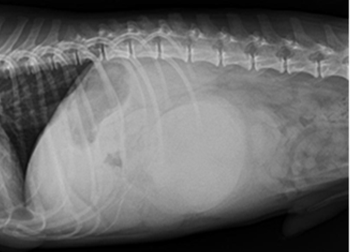

일반 X-Ray 촬영검사

-

흉부, 복부, 두부, 근골격계, 척추 촬영을 통해 환자 전반에 걸친 기본적인 정보를 획득할 수 있는 손쉬운 진단방법입니다. 본원 영상의학과의 X-선 검사장비는 디지털 검사장비를 도입하여 영상의 구현과 검사시간을 단축하였으며, 촬영시간은 물론 촬영 대기시간, 촬영에서 진단까지의 시간이 단축되어 환자 서비스 향상을 이룰 수 있습니다. 만일 촬영 후에 사진이 만족스럽지 않은 경우라 하더라도 촬영 후에 농도조정이 가능하기 때문에 불필요한 재촬영을 대폭 줄일 수 있습니다.